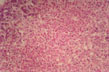

Councilmann body

Fig 26 - APOPTOSIS: This form of cell death appeares to be the normal way cells are renewed in every tissue.The cells condense,become round or spherical,separate from other cells,fragment and are phagocytized by histiocytes.This is the way lumina develop in tubular structures, limbs are fashioned, organs re reabsorbed in the metamorphosis of larvae and tailes are lost by tadpoles.The cells become dehydrated, and retain their organelles.There is no inflammatory reaction.In the liver the apoptotic cells are called Councilmann bodies.(1) (2).